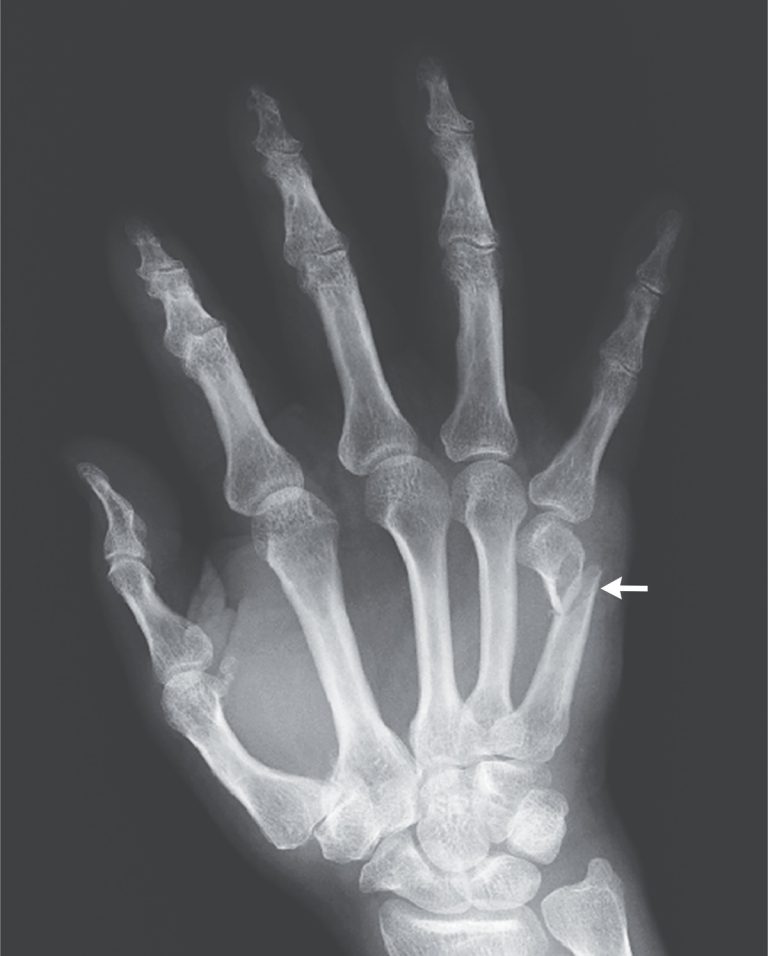

(a) Displaced subcapital fracture of the 5th metacarpal and of the base Return To Play After Metacarpal Fracture All patients returned to preinjury levels of competition, at a mean of 30.6 days for phalangeal fractures and 21.9 days for. All patients returned to preinjury levels of competition, at a mean of 30.6 days for phalangeal fractures and 21.9 days for. All athletes returned to their preinjury level of play without recurrence of fracture or wound complication. (1) basic. Return To Play After Metacarpal Fracture.

Greenstick fracture of the 5th metacarpal Image Return To Play After Metacarpal Fracture 39 injuries to the hand and 98 injuries to the finger. To our knowledge, there are no previous reports documenting return to play in elite football players after operative. (1) basic demographic data, (2) return to sport (rts) rates, (3) performance after rts, and (4) the difference in rts between players treated operatively versus conservatively. All patients returned to preinjury. Return To Play After Metacarpal Fracture.

Metacarpal fracture, Xray Stock Image C056/4178 Science Photo Return To Play After Metacarpal Fracture To examine finger, thumb, hand, wrist, and forearm fractures in the national hockey league (nhl) and determine: To our knowledge, there are no previous reports documenting return to play in elite football players after operative. 39 injuries to the hand and 98 injuries to the finger. (1) basic demographic data, (2) return to sport (rts) rates, (3) performance after rts,. Return To Play After Metacarpal Fracture.

Image Fracture of the 5th Metacarpal Neck MSD Manual Professional Return To Play After Metacarpal Fracture All patients returned to preinjury levels of competition, at a mean of 30.6 days for phalangeal fractures and 21.9 days for. (1) basic demographic data, (2) return to sport (rts) rates, (3) performance after rts, and (4) the difference in rts between players treated operatively versus conservatively. 39 injuries to the hand and 98 injuries to the finger. All athletes. Return To Play After Metacarpal Fracture.

Metacarpal fracture, Xray Stock Image C056/4177 Science Photo Return To Play After Metacarpal Fracture To our knowledge, there are no previous reports documenting return to play in elite football players after operative. (1) basic demographic data, (2) return to sport (rts) rates, (3) performance after rts, and (4) the difference in rts between players treated operatively versus conservatively. All patients returned to preinjury levels of competition, at a mean of 30.6 days for phalangeal. Return To Play After Metacarpal Fracture.